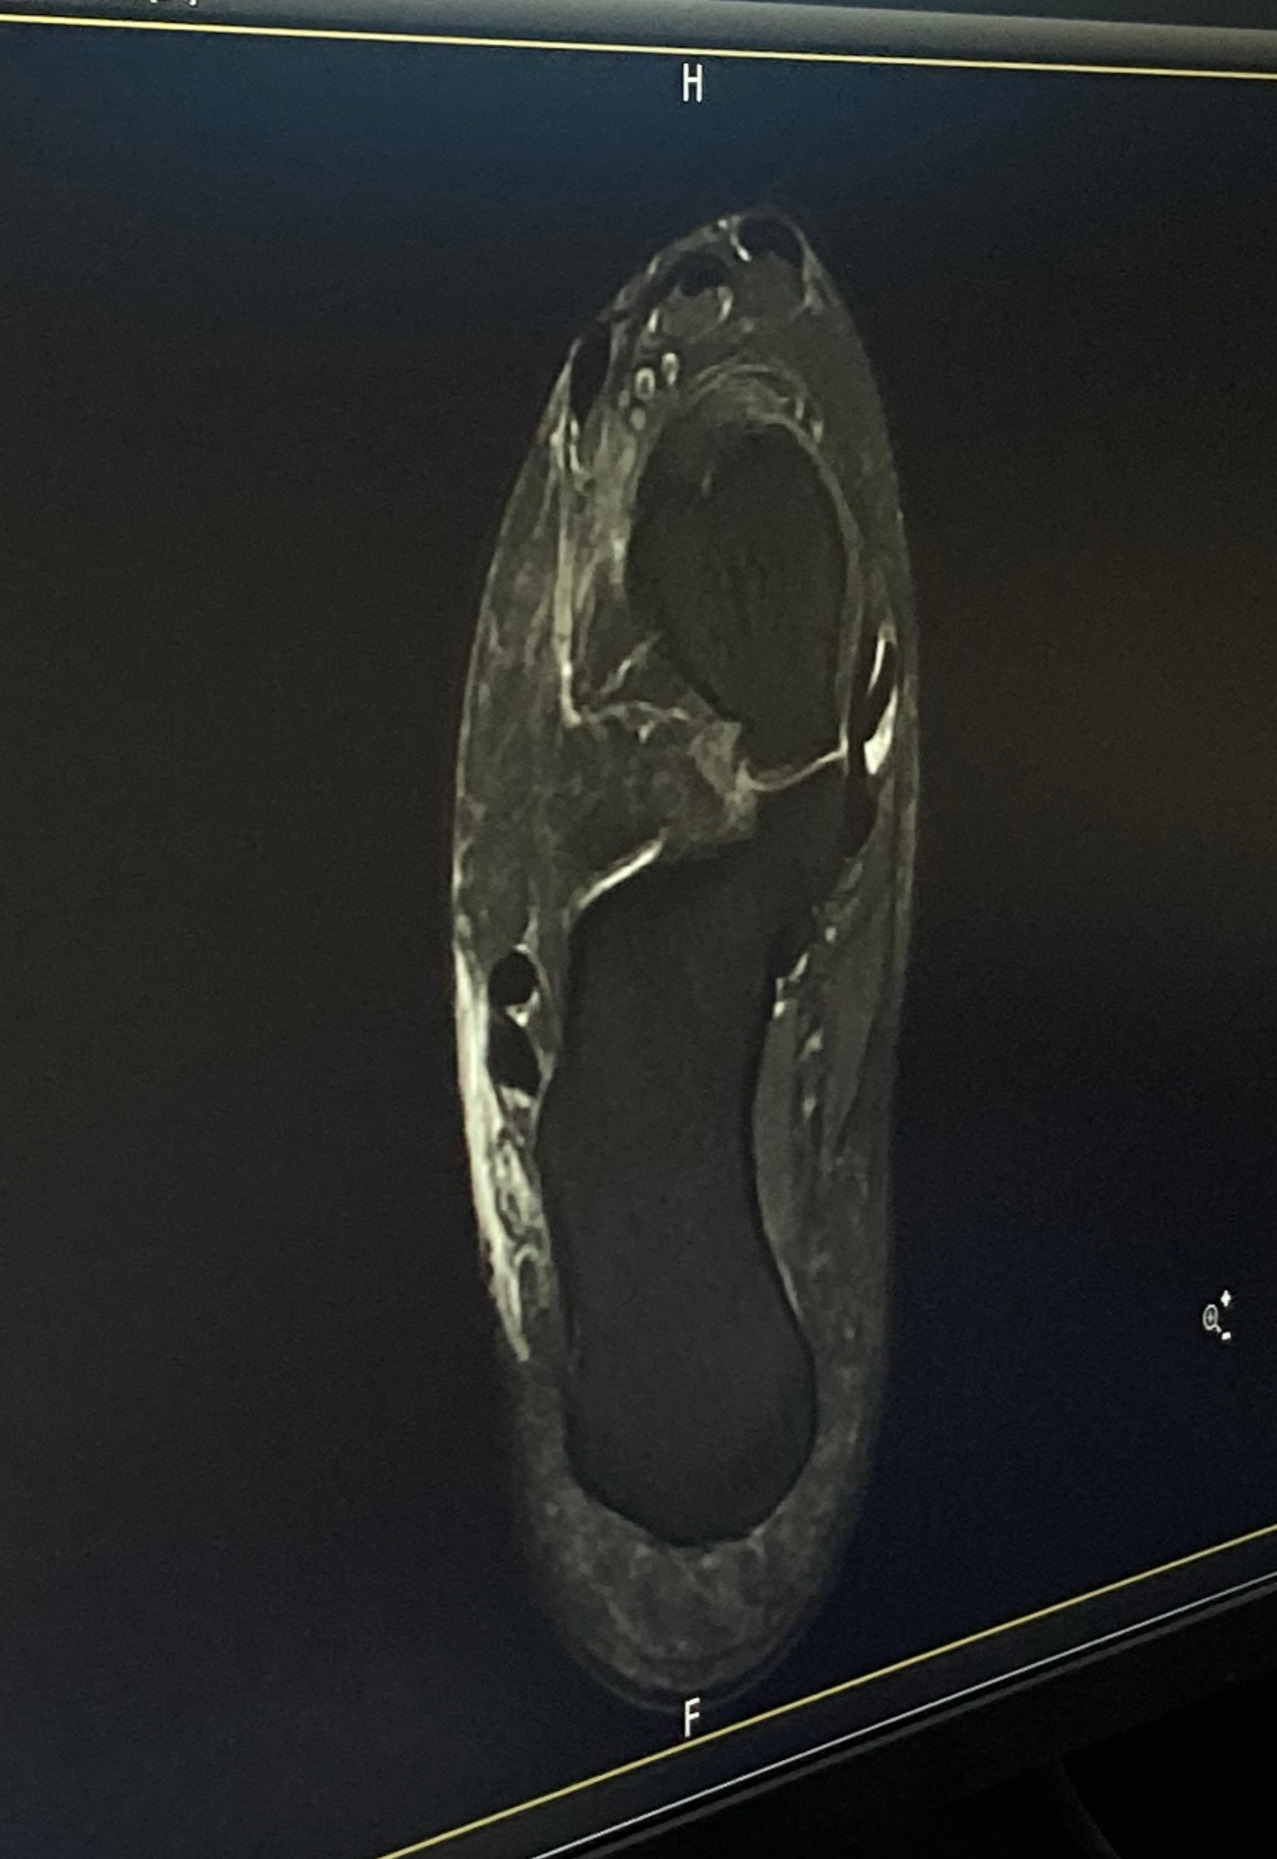

일주일이 지나도 발이 괜찮아질 기미가 보이지 않아 병원에 갔다.

KakaoTalk_20260118_222812628_20.jpg

지금 와서는 과잉진료라는 것을 알지만, 당시에는 만성적으로 아플까 겁이 나 의사가 권유하는대로 CT까지 찍었다.

결과적으로는 과부하로 인해 근육이 놀라고 염증이 생긴 것 뿐이었다.